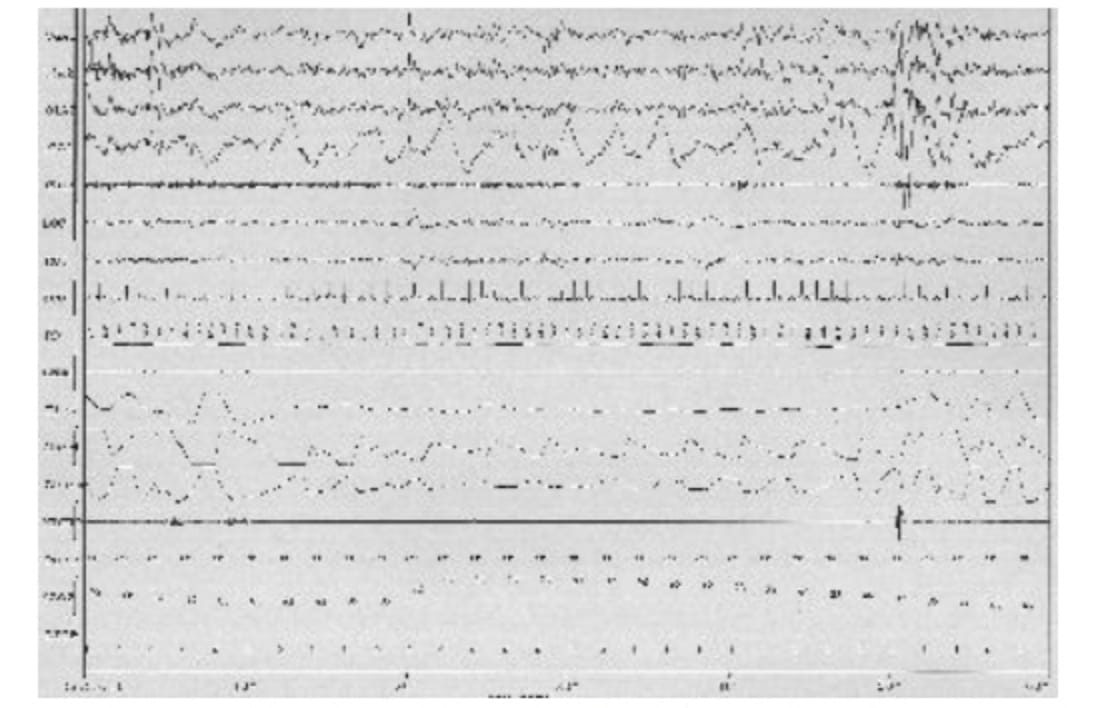

実際に専用個室に泊まっていただき、睡眠中の様子をモニターします。脳波、筋電図、眼球運動、心電図、呼吸運動、血液中の酸素飽和度、いびき音マイクなど多くのセンサーを装着しますが、これらがデジタル信号として記録され、呼吸障害の程度(無呼吸、低呼吸の有無、血液中酸素飽和度)睡眠障害の程度(睡眠の深さとリズム)などが評価できます。

実際の検査結果(閉塞性睡眠時無呼吸症候群)